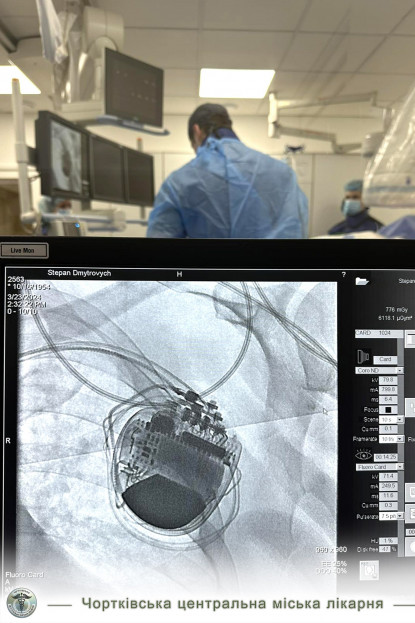

Днями у Чорткові відбулась історична подія для нашої медицини. У Чортківська центральна міська лікарня 69-річному пацієнту із Горішньої Вигнанки успішно імплантували в серце трикамерний кардіовертер-дефібрилятор. Оперативне втручання чортківські лікарі виконували спільно із фахівцями Національного інституту серцево-судинної хірургії ім. Амосова (м. Київ). Сам пристрій лікарня безкоштовно отримала від Міністерства охорони здоров’я, його вартість становить понад 300 тисяч гривень.

Пацієнту імплантували кардіовертер-дефібрилятор з метою відновлення та нормалізації порушень ритму серця, простими словами – він дозволить ослабленому серцю ритмічно битися. У пацієнтів, яким імплантували такий пристрій, навіть після перенесених інфарктів тривалість і якість життя значно поліпшується.

Операцію виконували лікар-хірург відділення лікування складних аритмій з рентгенопераційною Національного інституту серцево-судинної хірургії ім. Амосова Євген Перепека, а асистували йому фахівці Чортківської лікарні Тарас Сивак, Денис Хаблак, Марта Оробчук, Тарас Мазур, Роман Михальчук, Наталія Шишка.